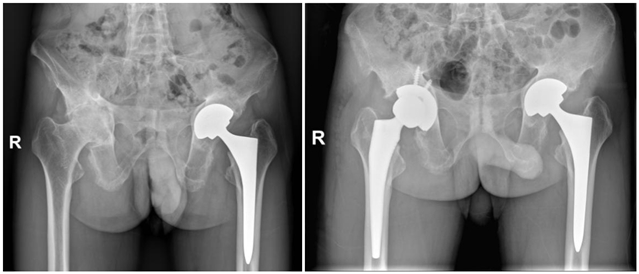

术前体态徐驰副主任根据患者病情,结合查体、影像学检查,认为只有实施手术治疗才能改善患者的行走功能,提高患者的生活质量。徐驰团队制定了详细的手术方案,患者目前最核心的问题是双侧髋关节疼痛、行走严重障碍,双侧髋关节屈伸功能明显受限,可行双侧全髋关节置换术,以人工关节替代损毁关节,重建结构,恢复功能。但由于患者股骨头和髋臼几乎已经骨性融合,手术难度较大、时间较长,为了降低手术风险,决定分两次对其进行全髋关节置换术。

脊柱出现骨性融合、 双髋关节间隙基本消失经过充分的术前准备,2021年7月9日,在徐驰主任的主刀下,为温先生实施了后外侧入路左侧人工全髋关节置换术。手术很顺利,取得了满意的效果。团队根据其康复的实际情况,于2022年8月24日对其右侧的髋关节也进行人工全髋关节置换术。

左髋置换术后、双髋置换术后术后第二天,温先生在没有助行器、没有拐杖辅助的情况下,自由下地行走,步态较之前明显改善,生活质量得到了明显提高,对患者以及家庭都是一个新的开始!